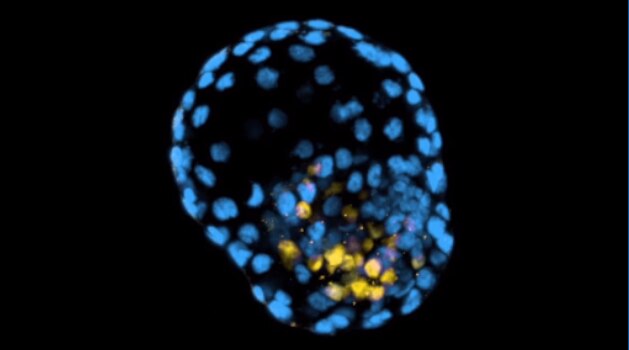

Researchers say it will help scientists study infertility, miscarriage and congenital diseases.(

Supplied

Scientists have created a model of human embryos from skin cells, in what is being hailed as a breakthrough in the study of infertility but has also raised serious ethical questions.

An international team, led by researchers from Monash University in Melbourne, was able to reprogram skin cells into three-dimensional structures akin to the early stages of human embryos.

Scientists successfully reprogrammed fibroblasts, or skin cells.